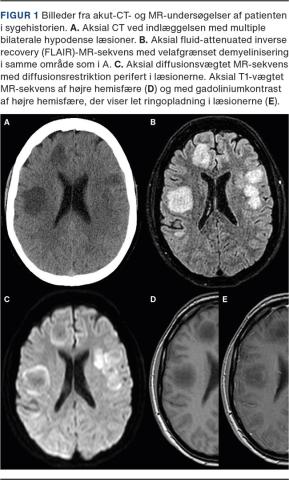

En 40-årig kvinde blev indlagt via neurologisk akutmodtagelse på grund af facialisparese og ændret personlighed. Hun var kendt med polycystisk ovariesyndrom, borderlinepersonlighedsforstyrrelser og årelangt misbrug af amfetamin. Initialt benægtede hun nogen form for stofmisbrug, men urinscreening var positiv for amfetamin. Ved objektiv undersøgelse fandt man central facialisparese, dysartri, diskret højresidig hemiparese og højresidig dysmetri. Akut-CT af cerebrum viste adskillige fokale hypodense læsioner, som gav mistanke om metastaser (Figur 1A).

I de efterfølgende dage sås gradvis forværring af tilstanden til svær tetraparese og akut nyre- og respirationssvigt. Ved MR-skanning af cerebrum med kontrast viste de før sete læsioner hyperintenst signal på en fluid-attenuated inverse recovery (FLAIR)-sekvens samt perifer diffusionsrestriktion og kontrastopladning (Figur 1B-E), hvilket var anledning til arbejdsdiagnosen akut demyeliniserende lidelse. Yderligere blod- og spinalvæskeprøver blev analyseret for reumatologiske og infektiøse årsager, inkl. hiv, syfilis, Borrelia og virus.

In this case report, a 40-year-old woman presented with altered mentation, central facial palsy and hemiparesis. Acute CT scan showed several hypodense, rounded areas in both hemispheres. Urine toxicology tested positive for amphetamine. Subsequent cerebral MRI had hyperintense T2-weighted fluid-attenuated inverse recovery (FLAIR) lesions in both hemispheres, indicating demyelinating disease. A biopsy was made from one of the lesions. The final diagnosis was toxic encephalopathy.